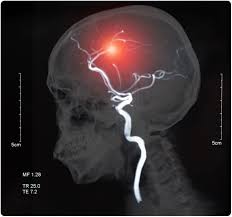

İnme (Serebellar Enfarkt):

Kimde? 60 yaş üstü, hipertansiyon, diyabet, sigara öyküsü olan erkeklerde ani başlayan vertigo durumunda "kırmızı alarm"dır.